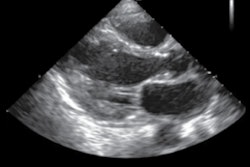

The FDA said that the software can be used to acquire standard views of the heart from different angles for 2D transthoracic echocardiography exams in adult patients.

The AI interface provides real-time feedback on potential image quality, can capture video clips, and automatically saves the best video clip acquired from a particular view, the FDA said.